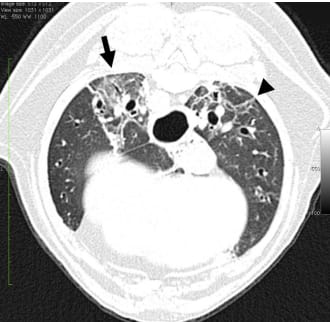

A transverse HRCT image at the level of caudal lung lobes in an 11-year-old WHWT with CIPF and a PaO2 of 57 mm Hg. Areas of GGO (arrow) and traction bronchiectasis (arrowhead) are seen dorsally. The images were obtained under general anesthesia. (Courtesy of Anu K. Lappalainen, DVM, PhD, University of Helsinki, Finland.)

CIPF is characterized by mature diffuse interstitial fibrosis with occasional foci of cellular, immature fibrosis resembling both nonspecific interstitial pneumonia (NSIP) and usual interstitial pneumonia (UIP) in humans. Dogs typically present with exercise intolerance, cough, and Velcro crackles, though clinical signs are variable. High-resolution computed tomography reveals ground-glass opacities and mosaic attenuation, among other patterns. Biomarkers such as endothelin-1, PIIINP, and matrix metalloproteinases in serum and BALF show promise for diagnosis and monitoring. Pulmonary hypertension is a common complication. Despite symptomatic treatments, including corticosteroids, theophylline, and sildenafil, no curative therapy exists. Median survival after diagnosis is approximately 11 months.